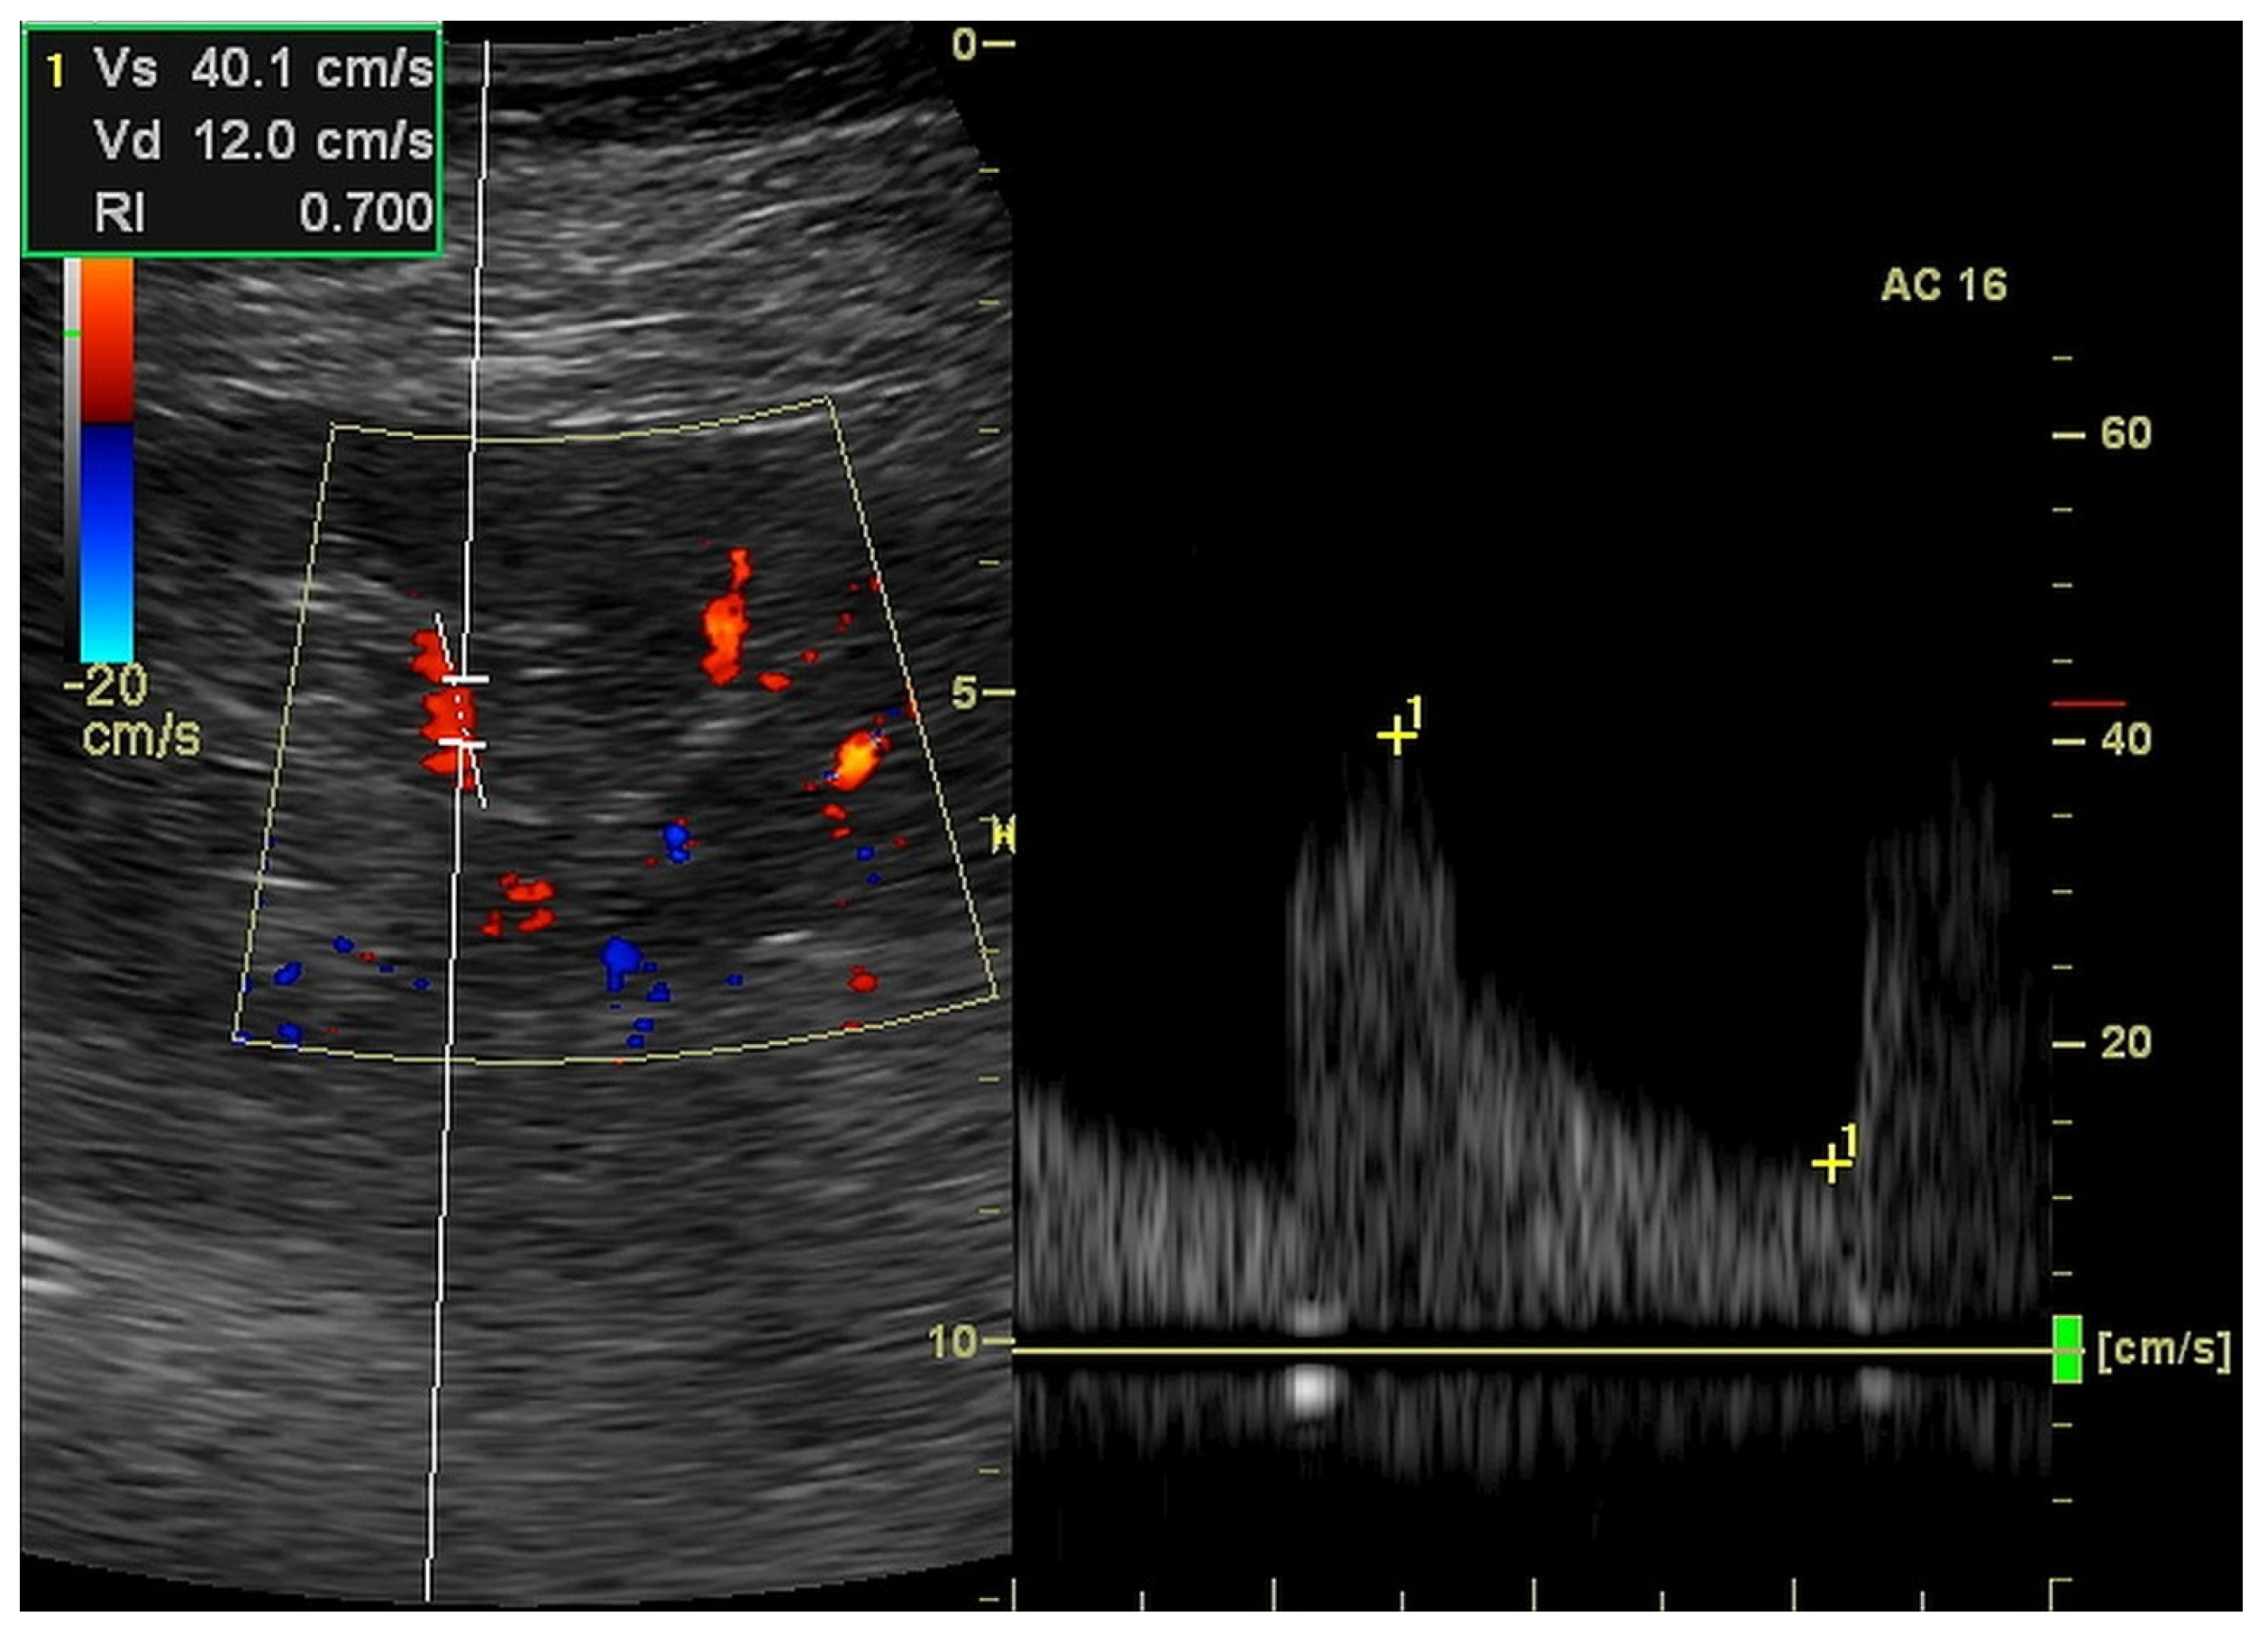

| ACC (m/s2) | 7.22 | 2.58 | 6.90 | 2.90 |

| ACT (ms) | 36.2 | 8.22 | 37.9 | 11.8 |

| RI (ratio) | 0.701 | 0.115 | 0.721 | 0.169 |

| EDV (cm/s) | 13.6 | 5.6 | 12.2 | 9.7 |

| dRI (ratio) | 0.735 | 0.168 | 0.760 | 0.205 |

| dPI (ratio) | 1.433 | 0.582 | 1.430 | 0.930 |

| dRCP (cm/s) | 0.483 | 0.452 | 0.303 | 0.529 |